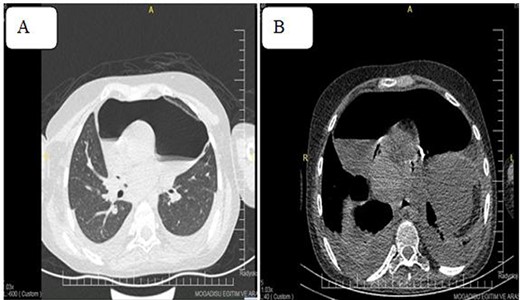

Despite therapeutic Pericardiocentesis, the patient’s clinical has not resolved. Therefore, computed tomography (CT) of the chest was requested, which revealed a thickened pericardium with pneumopericardium, as shown in Fig. 4.

Pneumoprecadium on chest CT (A) and moderate pleural effusion (B).

The presence of air-fluid levels in the pericardium can be visualized via chest X-rays and CT scans [9]. Unstable patients with penetrating chest injuries and pneumopericardium necessitate emergent surgery [10]. The CT scan of our case revealed a thickened pericardium with pneumopericardium; similarly, an emergency pericardiectomy was performed, and the patient was transferred to the intensive care unit.